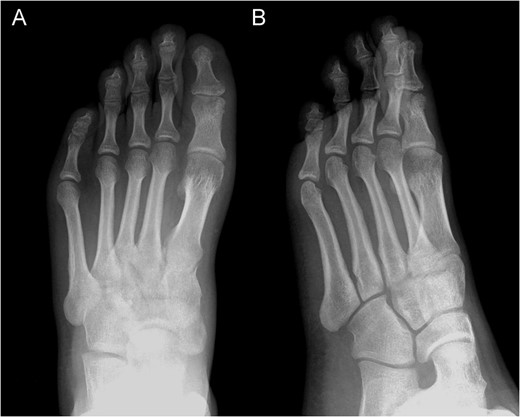

Posterior–anterior (A) and oblique (B) X-ray imaging of the left forefoot, showing the integration of the bone graft after 6 weeks.

The pain decreased post operation with no rest-pain after 3 weeks. After 6 weeks, the X-ray revealed radiological signs of consolidation which allowed for weight bearing. Four months after surgery, the patient returned to sport without limitations.